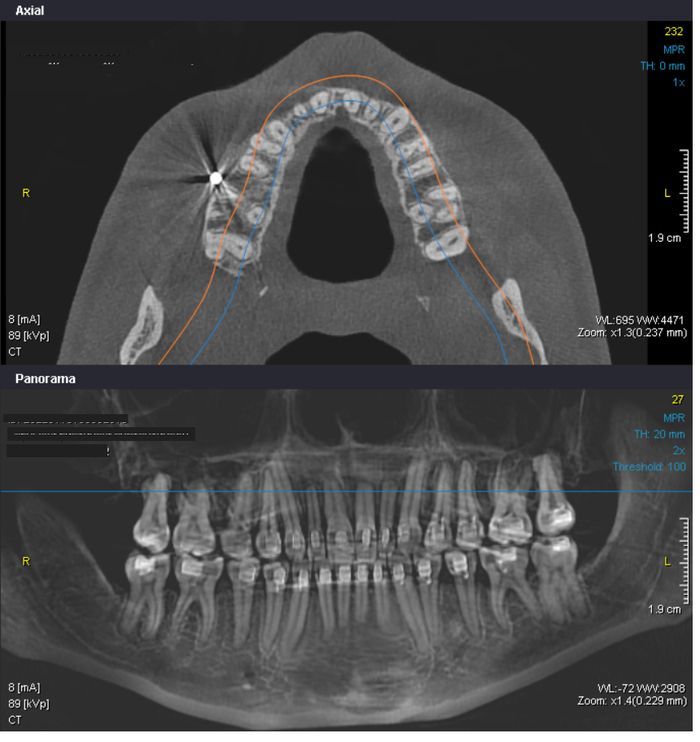

Осложнения после ортодонтического лечения

Всем привет. Я девушка, 33 года и в этом году мне сняли брекеты, которые я носила 3,5 года. Причина по которой я носила брекеты - это большая скученность и неправильный прикус, изначально у меня были все зубы абсолютно здоровыми, несколько небольших пломб стояли, здоровые кости, но тонкий биотип десны и костей.

После брекетов я получила осложнения, который видны на КТ. Разместив снимки КТ в ИИ, тот настоятельно мне порекомендовал нарастить костную ткань, однако, обратившись к пародонтологу я узнала, что к своим родным зубам нарастить костную ткань нельзя, особенно в районе резцов и мне предложили только закрытие рецессий, когда они появятся. В связи с чем, я хотела бы обратиться за помощью, помогите пожалуйста разобраться в моих снимках и понять, как правильно действовать в данной ситуации, чтобы сохранить свои родные зубы как можно дольше. Буду благодарна за профессиональное мнение и рекомендации. (Фотография зерькальная)